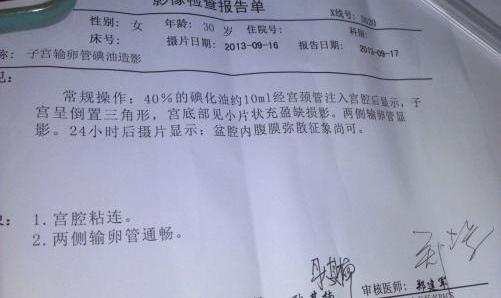

但都没有怀孕.第三个月自己决定做造影.

跟大家分享一下我的输卵管造影经历

输卵管造影2月19日做的造影2月20

你好,我做造影检查左侧输卵管梗阴,右侧

不孕,做了造影疑似宫腔粘连了帮忙看下